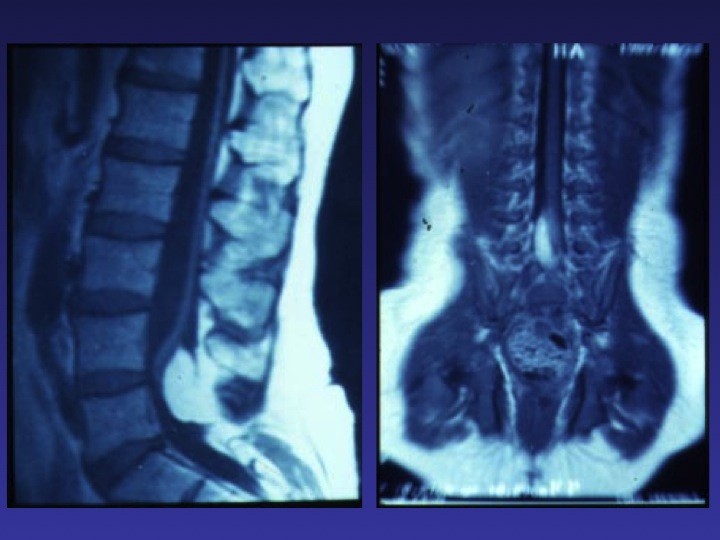

TABLE RONDE – La moelle attachée de l’enfant et de l’adolescent : diaporama 1

TABLE RONDE – La moelle attachée de l’enfant et de l’adolescent : diaporama 2

TABLE RONDE – La moelle attachée de l’enfant et de l’adolescent : diaporama 3